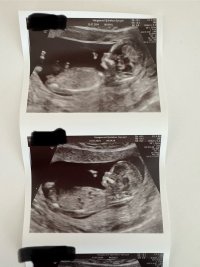

Var på TUL i dag 13+3. Hun mente det kunne se ut som jente men ville ikke bekrefte noe. Hva tror dere? :)

Jeg har ikke peiling på sånt! Men jeg synes det ser ut som en gutt, eller.. jeg vet ikke:smiley-ashamed004